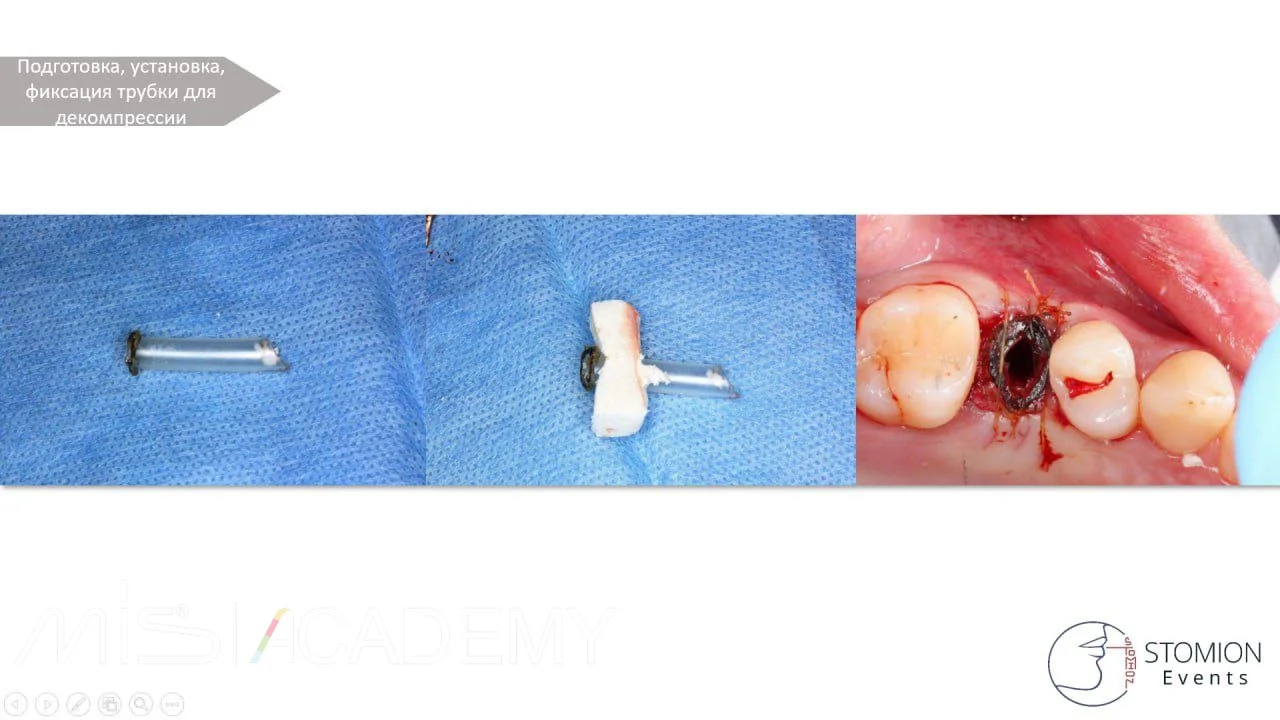

— Далее подготовили трубку для декомпрессии, установили и зафиксировали «Кетгутом».